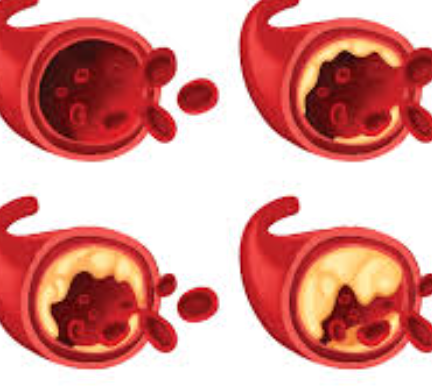

담석은 담낭이나 담도 내에서 형성되는 고체 물질입니다. 대부분 담석은 콜레스테롤, 담즙산, 또는 양 세균성 담석으로 분류됩니다.

담석 종류

1. 콜레스테롤 담석

콜레스테롤이 담낭 내에서 과도하게 농축되어 콜레스테롤 결정이 형성되는 경우입니다. 콜레스테롤 담석은 주로 혈중 콜레스테롤 수치가 높은 사람들에게서 발생합니다.

2. 담즙산 담석

담즙산이 과도하게 농축되어 담낭 내에서 결정을 형성하는 경우입니다. 담즙산 담석은 일반적으로 담낭에서 담즙의 pH가 증가하여 발생할 수 있습니다.

3. 양 세균성 담석

담도 내에서 세균이 성장하여 담석을 형성하는 경우입니다. 이는 담도 내에 염증이나 감염이 있는 경우에 발생할 수 있습니다.

담석은 보통은 작고 작은 결정으로 시작해 담도를 차단할 수 있습니다. 이로 인해 복통, 구토, 설사 등의 증상이 발생할 수 있습니다. 일부 경우에는 담석이 담도를 차단하여 심각한 감염을 유발할 수도 있습니다.